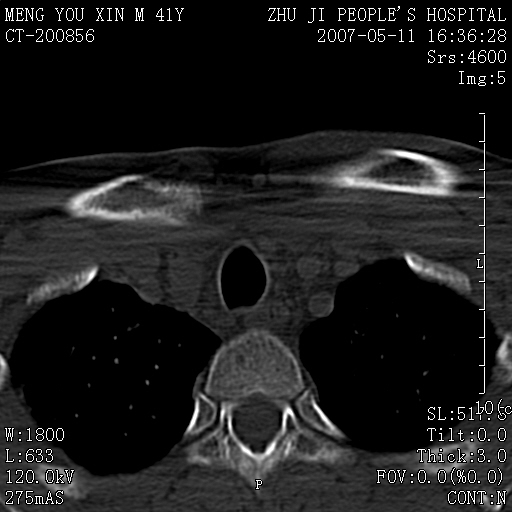

标题: CT8190:左锁骨胸骨端骨病,请会诊.

一周前左肩部酸痛,三天前颈部扭伤,后颈部摄片示颈椎病.现胸锁关节处肿痛明显.无发热.自诉三年前车祸安全气囊弹出.

左侧锁骨近端膨大,骨皮质中断,并见少许骨膜反应,内见破坏,边缘见筛孔征,无硬化.因此考虑骨巨细胞瘤可能.

双侧胸锁关节未见明显异常改变。

1,不支持结核,此例胸壁肿胀不明显,锁骨后方是局限性肿物而非脓肿,考虑为恶性肿瘤2,左侧锁骨近端膨大,骨皮质中断,并见少许骨膜反应,内见破坏,边缘见筛孔征,无硬化.因此考虑骨巨细胞瘤可能.